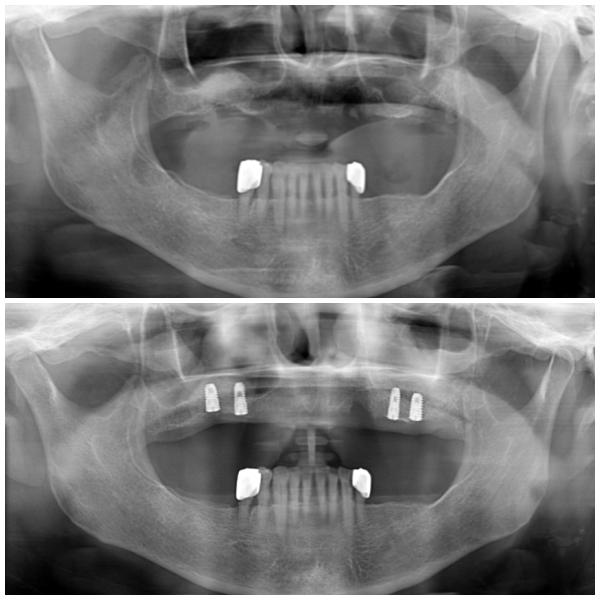

위쪽 전체틀니를 사용하고 계셨으며 틀니가 유지되는 부분이 없어 자꾸 탈락되는 불편함으로 " 임플란트를 이용한 부분틀니 " 작업으로 계획을 하셨습니다.

오랜 틀니 사용으로 인해 잇몸뼈가 많이 줄어들었으며, 임플란트를 식립하기에는

남은 뼈의 길이가 부족한 상태였습니다.

상악동 거상술 이라는 뼈 이식을 통해 충분한 길이를 확보하고

임플란트를 식립하였습니다.

수술 후 약간의 부종만 있을 뿐 다른 부작용은 없으셨습니다.